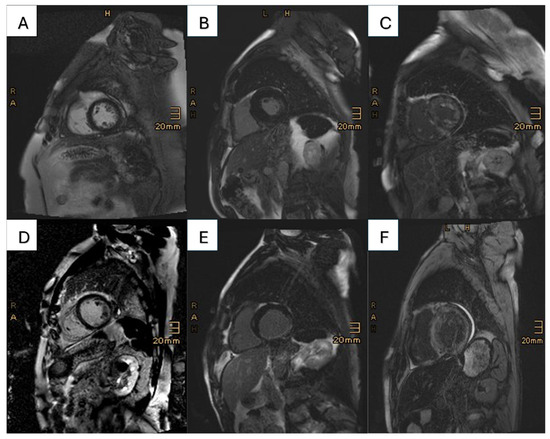

2.4. Cardiac Magnetic Resonance Imaging

Assessment of Coronary Artery Disease

| Type of LGE (%) | <0.001 | |||

| No LGE | 9 (4.7) | 2 (3.2) | 7 (5.5) | |

| Amyloid-specific LGE | 158 (83.2) | 46 (74.2) | 112 (87.5) | |

| postischemic LGE | 12 (6.3) | 11 (17.7) | 1 (0.8) | |

| Insertion points | 5 (2.6) | 2 (3.2) | 3 (2.3) | |

| Unspecific LGE | 4 (2.1) | 1 (1.6) | 3 (2.3) | |

| No contrast agent given | 2 (1.1) | 0 (0.0) | 2 (1.6) | |